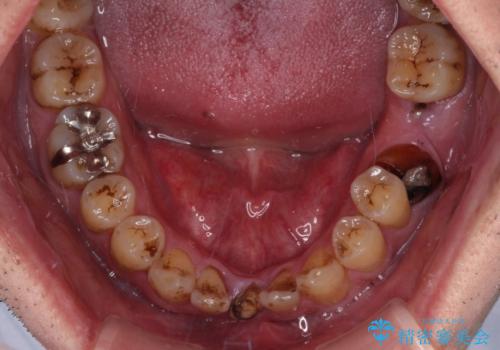

- むし歯治療途中で放置された歯が多く、スペースができたり歯が寄って来たりしているのを気にして来院された患者様です。

矯正治療を行いながら、欠損部はインプラントによる補綴治療を希望されたため、補助装置を用いたワイヤー矯正によりスペースを確保しながら歯列を整え、適宜インプラントを埋入していくこととしました。

下顎前歯にインプラントを2本埋入するのは非常に困難であり、どうしても歯肉位置に土台の金属色が見えてしまう仕上がりとなりました。無理をせずに1本のみの埋入とするか、ブリッジを提案しましたが、患者様の強い希望により、2本埋入することとなり、大変満足していただけました。